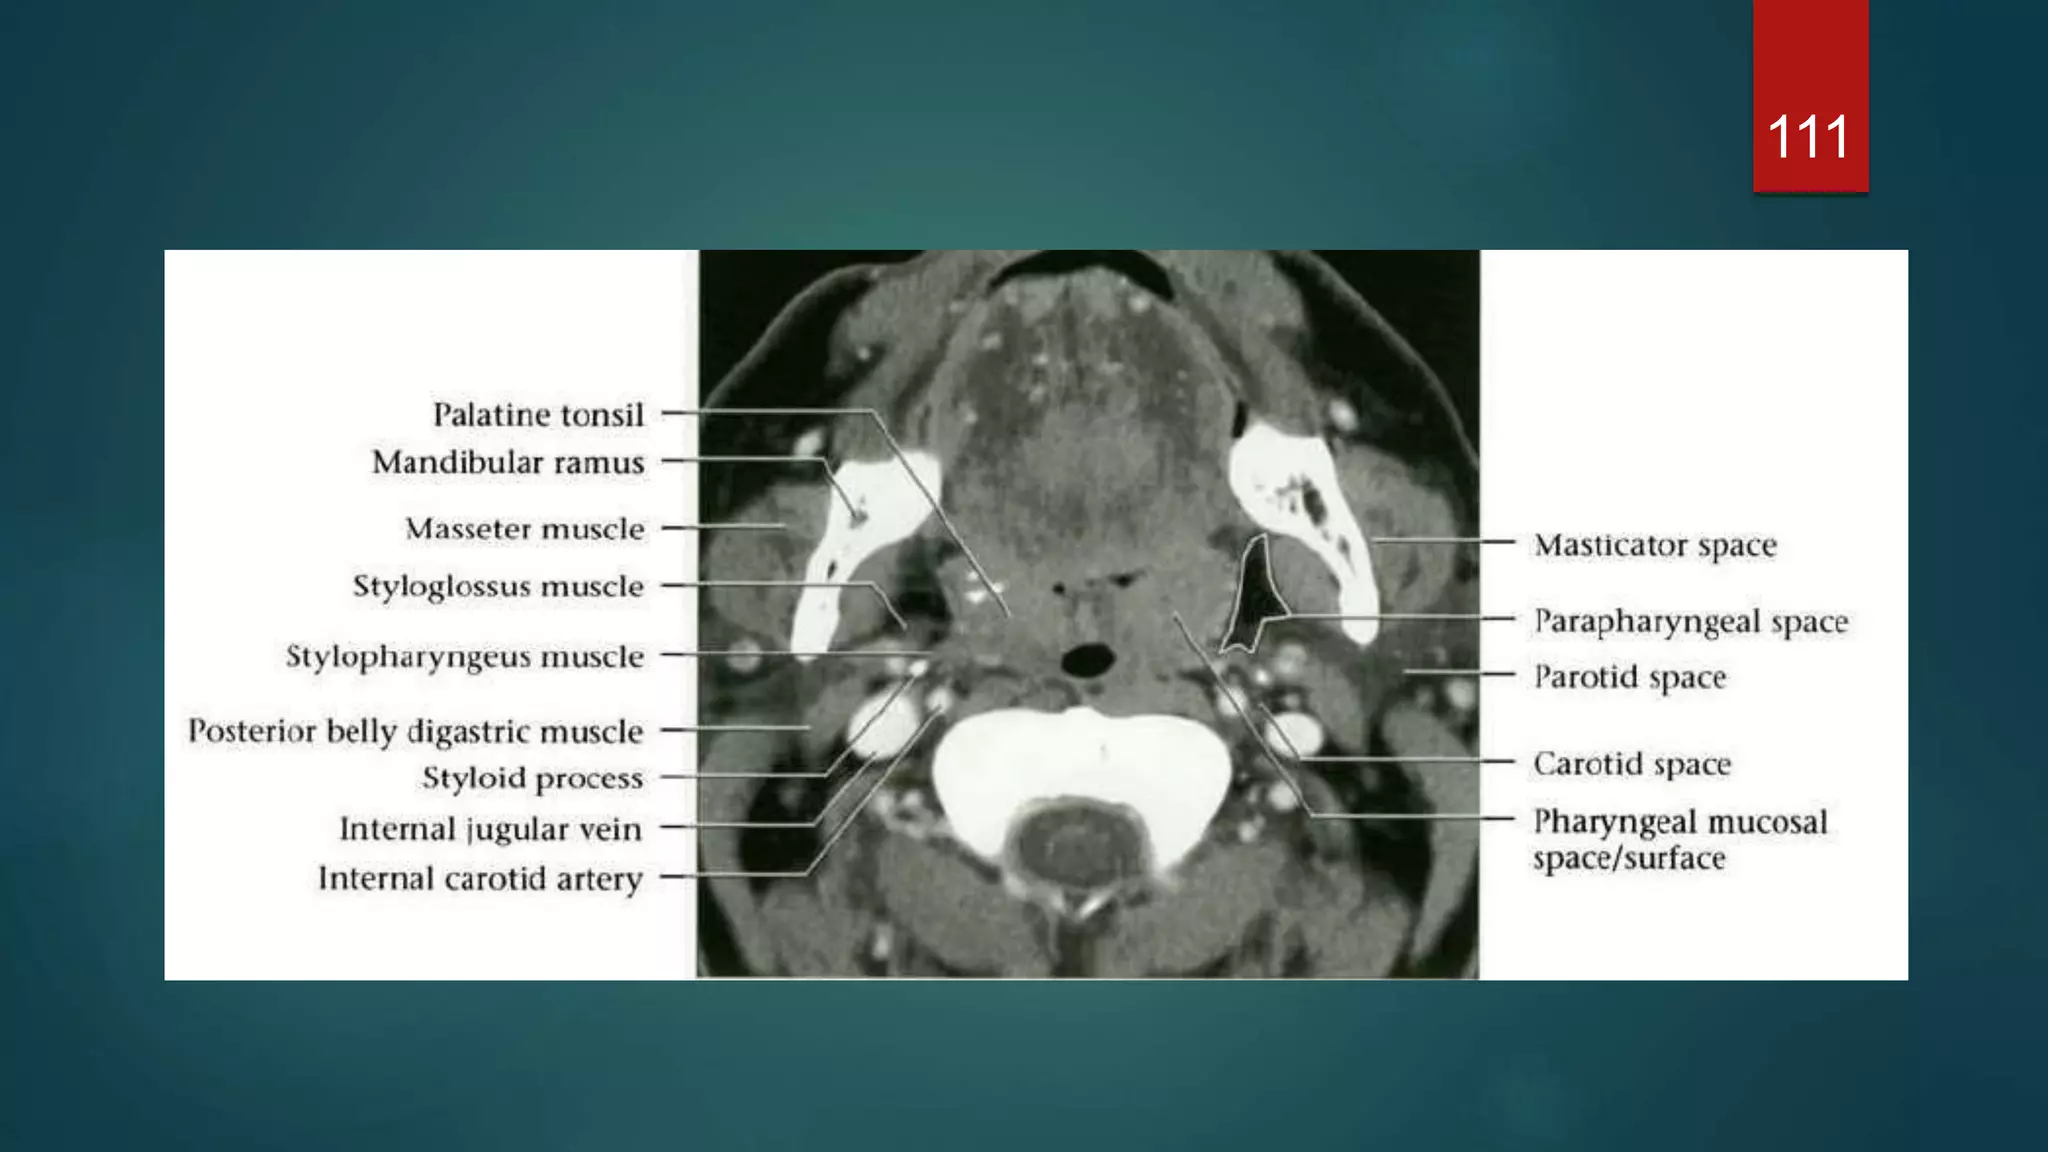

111